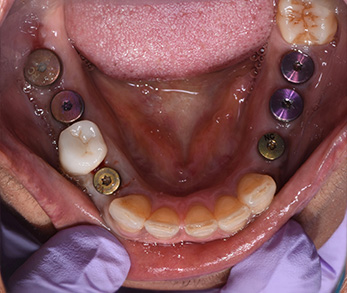

Dental Implants

Before

After

Smile Makeover